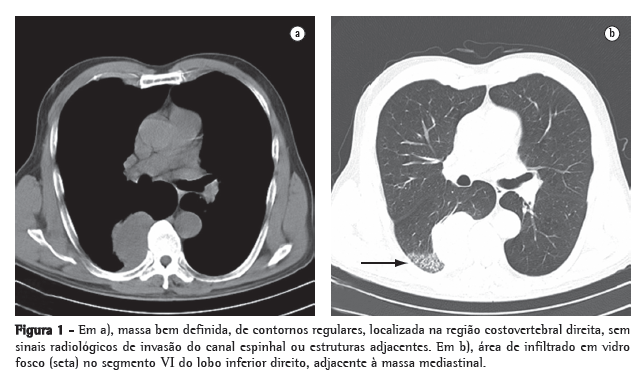

Radiograma de tórax evidenciou atelectasia de lobo inferior do pulmão esquerdo, com elevação da cúpula diafragmática em mesmo lado e desvio de traquéia para esquerda e possível lesão em traquéia. Pela gravidade da situação clínica, o paciente foi internado após as primeiras medidas terem sido tomadas no serviço de emergência para estabilização clínica. Fibrobroncoscopia evidenciou uma extensa massa móvel, com obstrução quase total, no terço inferior da traquéia, junto à emergência do brônquio principal esquerdo (Figura 1). Tomografia computadorizada de tórax confirmou a presença de obstrução tumoral traqueal (Figura 2). Broncoscopia rígida foi indicada para realização de tunelização da lesão, o que foi efetivamente feita com retirada de 90% da lesão. Após este procedimento, o paciente apresentou relevante melhora da dispnéia e da tosse.